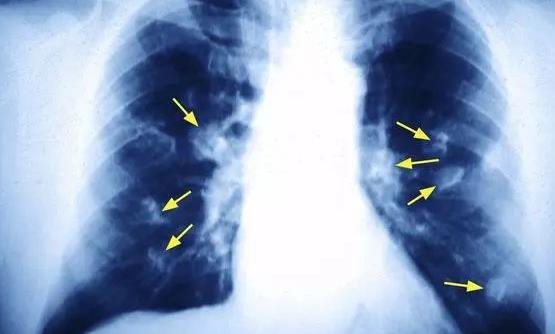

我國國家癌癥中心的最新報告顯示,肺癌是女性第二高發的癌癥,僅次于乳腺癌。40-50歲女性中肺癌患者人數已經接近男性,達到了1:1的比例。但是國內女性的吸煙率很低,為何發生肺癌的概率卻如此“不協調”地高呢?下面跟隨360常識網了解一下吧!

對肺癌患者長達5年的追蹤病因調查發現,70%的男性肺癌患者死于吸煙病因,只有18%的女性患者因吸煙或長期被動吸煙致肺癌。

當然是做飯!調查發現,在不吸煙的女性肺癌患者中,超過60%的女性不僅在家做飯,還在廚房中長期吸入油煙。

在非吸煙女性肺癌危險因素中,超過60%的女性長期接觸廚房油煙;有32%的女性燒菜喜歡用高溫油煎炸食物,同時廚房門窗關閉,廚房小環境油煙污染嚴重;25%的女性家中廚房連著臥室,冬天又很少開窗,高溫油煙久久不散,甚至睡覺時也在吸油煙!

調查表明,這種病因在中老年女性肺癌患者中特別突出,危險因素達到了正常人的2-3倍。